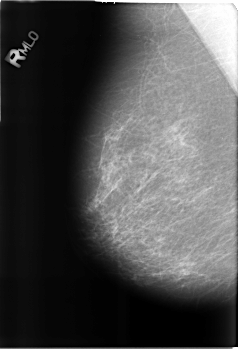

Volume: benign_without_callback_01 Case: B-3214-1

B_3214_1.RIGHT_MLO

LEFT_MLO LINES 4480 PIXELS_PER_LINE 3088 BITS_PER_PIXEL 12 RESOLUTION 50 OVERLAY

FILE: B_3214_1.LEFT_MLO.OVERLAY

TOTAL_ABNORMALITIES 1

ABNORMALITY 1

LESION_TYPE CALCIFICATION TYPE EGGSHELL DISTRIBUTION N/A

ASSESSMENT 2

SUBTLETY 4

PATHOLOGY BENIGN_WITHOUT_CALLBACK

TOTAL_OUTLINES 1

BOUNDARY